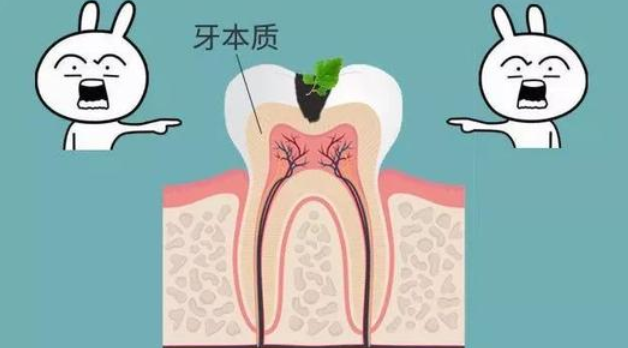

蛀了三分之一时,已经龋坏到牙本质了,牙齿遇冷热酸甜等会有刺激性疼痛。此时,龋齿的发展速度非常迅速的,一定要高度重视。

蛀到一半以上后,这时已经是蛀牙重度晚期了!由于没有在早中期的及时处理,蛀牙部分已经发展到牙神经,这个时候肯定要进行牙神经处理了。